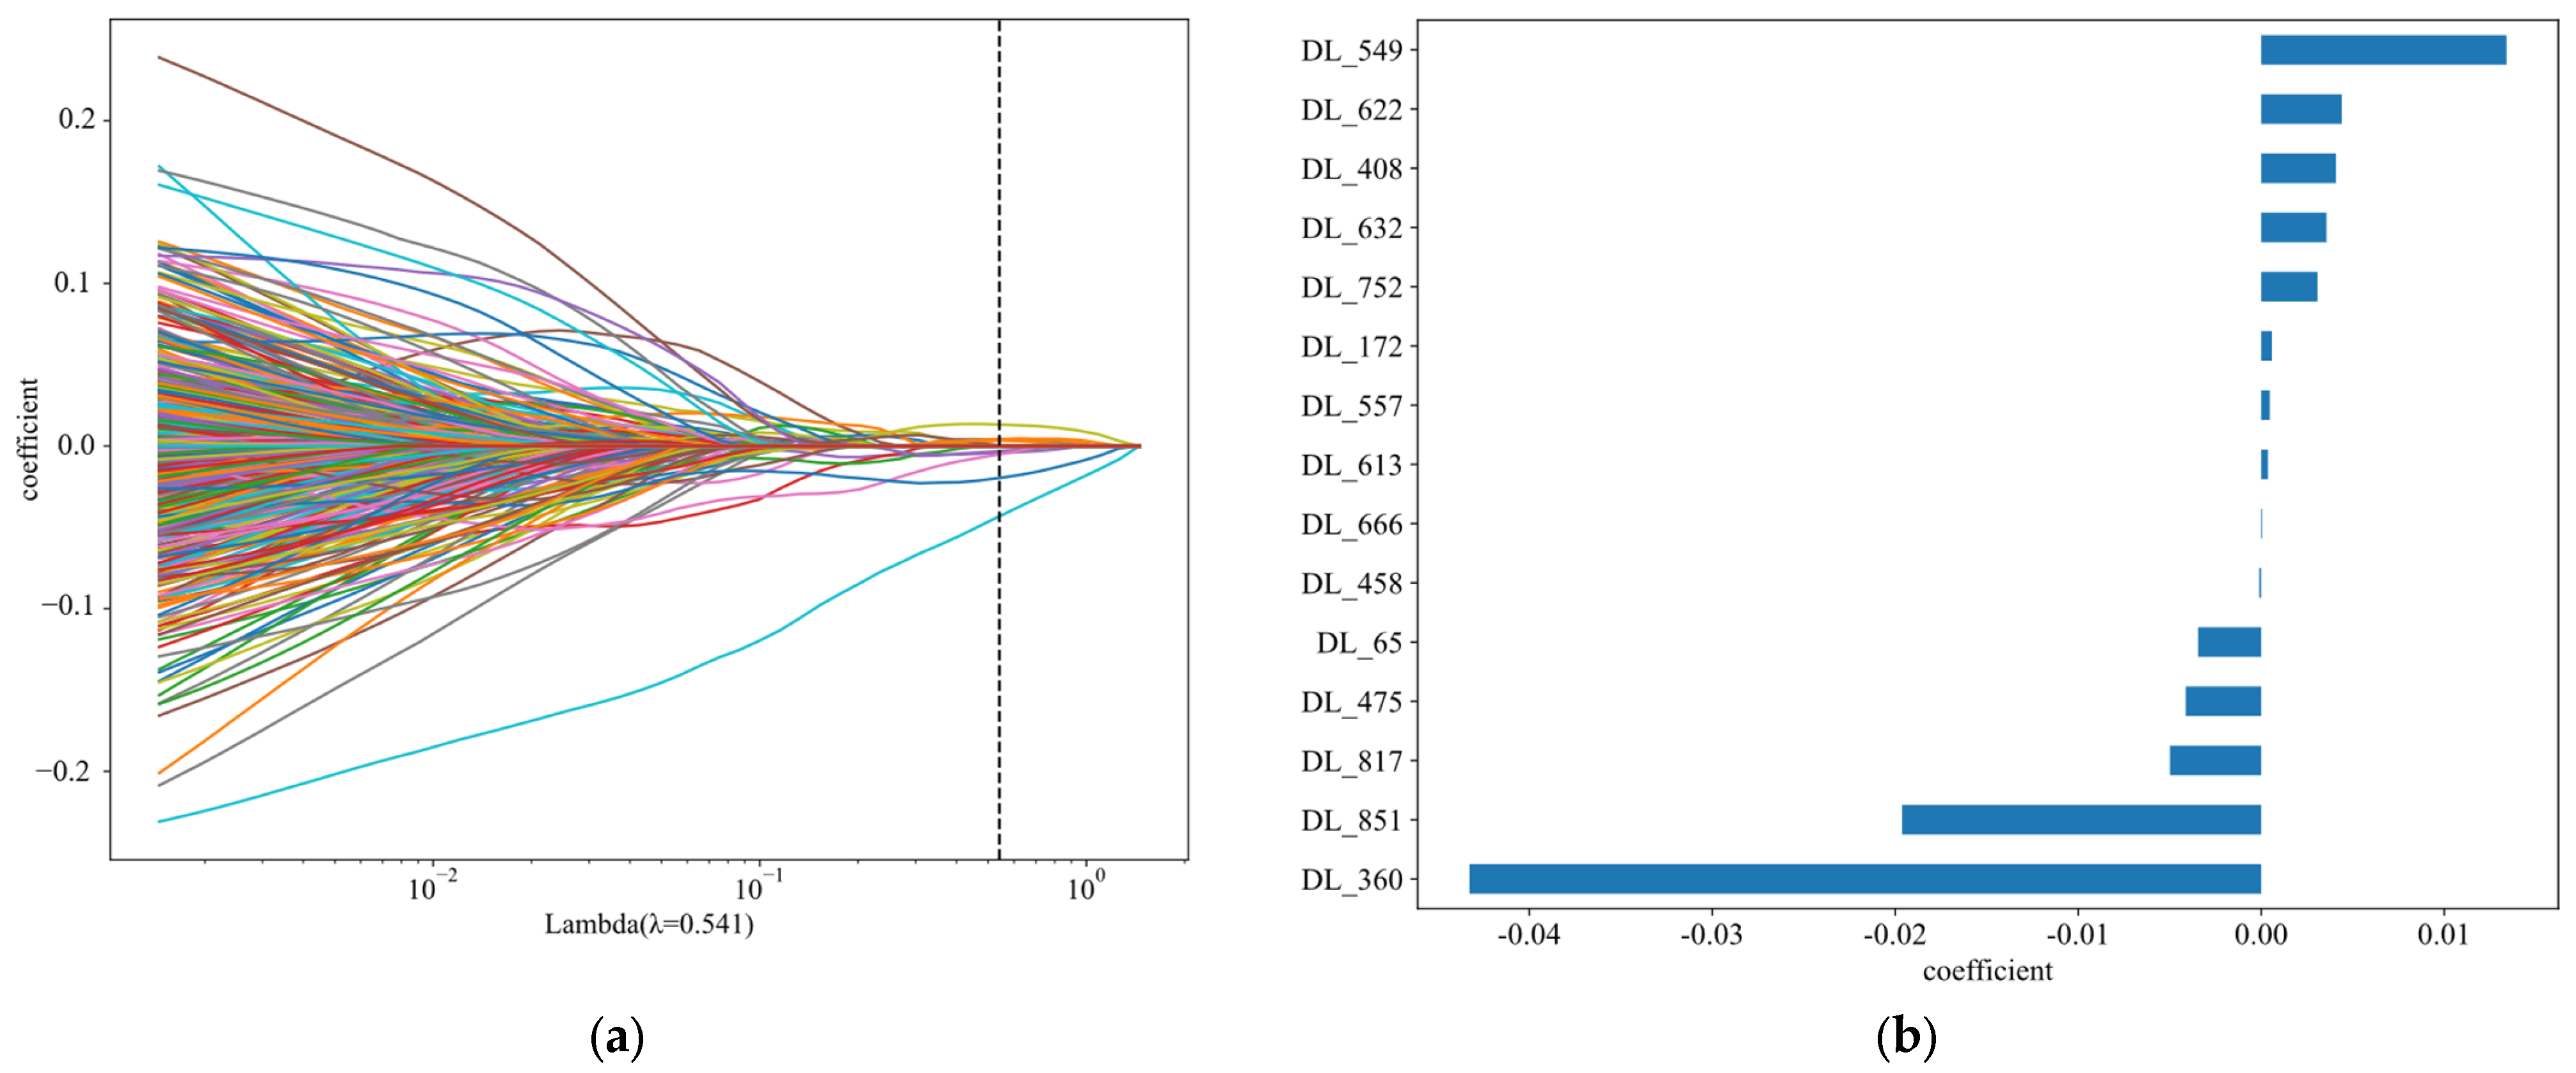

5.2. Survival Time Prediction